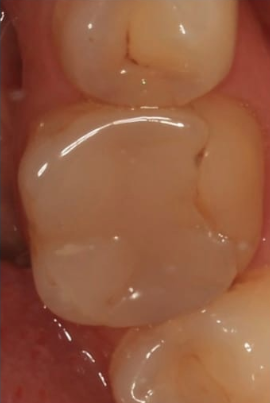

1 работа в портфолио

В работе использую цифровые технологии. Планирую и моделирую зубные коронки или протезы на компьютере в специальной программе. Передаю по интернету на специальный станок, где их вытачивают. Для пациентов это хорошо тем, что коронки получаются намного точнее и удобнее.